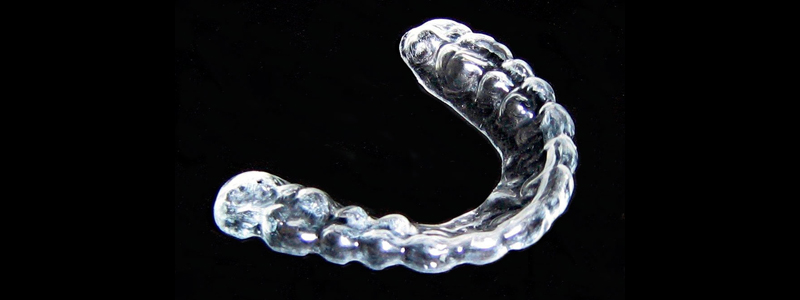

El bruxismo se conoce comunmente como "apretar los dientes" y es una patología que puede provocar dolores de cabeza, de mandíbula y desgaste de las piezas dentales entre otros...

Para paliar los problemas que conlleva el bruxismo, que es cuando una persona tiende a apretar o rechinar los dientes, podemos disponer de forma rápida, simple y eficaz para...

En Clínica Tornel ofrecemos servicios de Odontología, Podología, Fisioterapia y Osteopatía. Dentro de la disciplina de Odontología que ofrecemos a nuestros pacientes, con el...